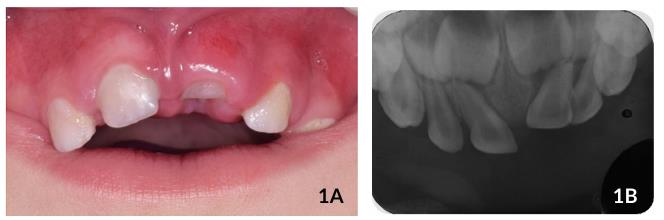

Durante a primeira consulta, foram realizados exames clínico e radiográfico, observando-se inchaço no tecido gengival na região dos incisivos superiores, dentes #61 intruído, com um terço de coroa visível (grau II) e leve intrusão do dente #62, com mais de um terço de coroa visível (grau I) (Figura 1A).

Radiograficamente, (radiografia periapical anterior modificada e radiografia lateral de Fazzi), os dentes #61 e #62 apresentavam- se sem fratura da tábua óssea e lesão dos germes dos dentes permanentes (Figuras 1B e 2). Sendo assim, o tratamento de escolha foi aguardar e acompanhar a reerupção espontânea dos dentes afetados.

Ao exame clínico após 7 dias, foram observados vermelhidão e inchaço da mucosa adjacente. Não houve mobilidade dos dentes #61 e #62, e o dente #61 apresentava um terço de coroa visível. Ao exame clínico e radiográfico após duas semanas, foi possível observar leve reerupção dos elementos dentários envolvidos (Figuras 3A e 4B).

Figuras 3A y 3B Aspectos clínicos e radiográficos após 2 semanas de acompanhamento ilustrando o início do processo de reerupção dentária.